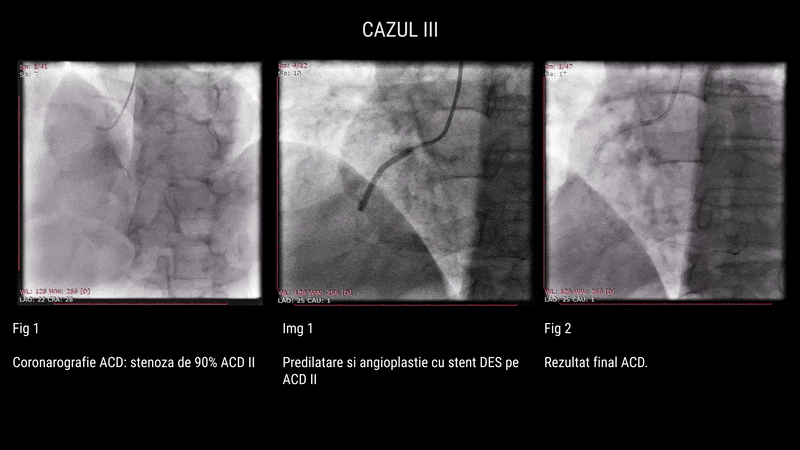

Al treilea pacient, în vârstă de 62 de ani, hipertensiv și dislipidemic, cunoscut cu leziuni tricoronariene (ocluzii pe ACD, stenoze critice pe LAD și ACX), a fost internat pentru angioplastie. Intervenția a presupus rotablație pe ACX și TACS–LAD, cu implantare de 4 stenturi DES facilitată de rotablație, POT și Kissing Balloon. Aspectul angiografic final a fost satisfăcător, cu flux TIMI 3 menținut și fără complicații.